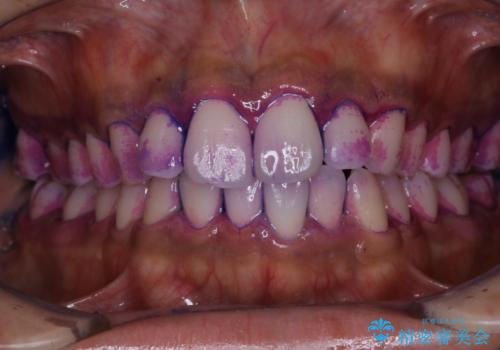

- 特に症状など気になるところはないが、メンテナンスして欲しいとのことでした。染め出しをしてのブラッシング指導とPMTC30分コースを行いました。

染め出しをすると、現在付着しているプラークを確認できて、今後の正しいハミガキの方法を知るチャンスとなります。